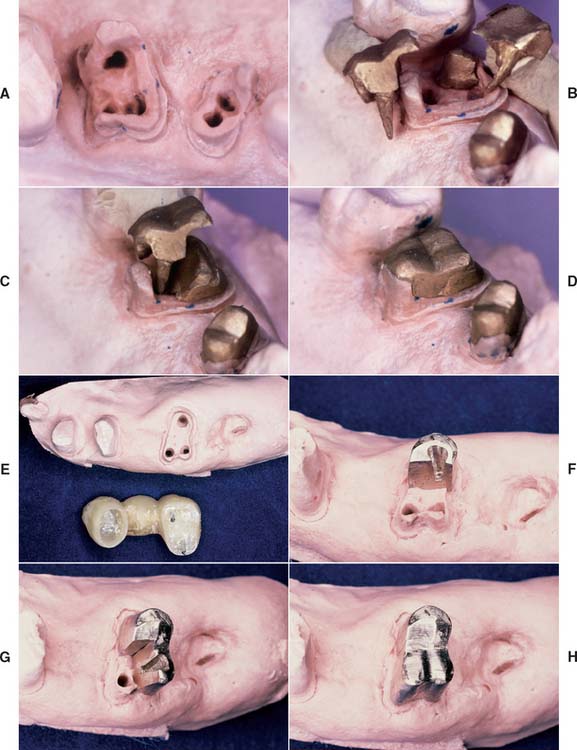

Although it is possible to restore a severely compromised molar with three or more missing cusps with multiple posts and amalgam, the tooth’s overall importance must be assessed, as the prognosis of such teeth is often guarded. If retaining the tooth is crucial and optimal strength is needed, a multipiece cast core can be used (made in sections that have different paths of withdrawal) (Fig. 12-20). An alternative preparation method for a posterior tooth is selecting the canals that are widest (normally the palatal of maxillary molars and the distal of mandibular molars) for the major post and then preparing short auxiliary post spaces in the other canals with the same path of withdrawal (Fig. 12-21).

Fig. 12-20 A to F, Cast cores for posterior teeth can be made in interlocking sections, with each section having its own path of withdrawal.

Fig. 12-41 A to D, Multipiece post and cores can be made by the indirect technique, waxing each section to ensure that no undercuts are created. E to H, Alternatively, interlocking sections can be made, but this complicates the laboratory phase.

Using dovetails to interlock the sections makes the procedure more complicated and is probably of limited benefit, especially because the final buildup is held together by the fixed cast restoration.